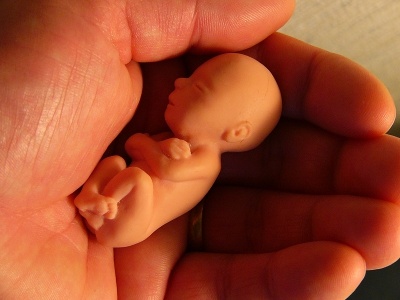

Cituji Gandalf: A pro pořádek - potrat není vražda. Je to odstranění shluku buněk

A pro pořádek

takhle vypadá shluk buněk zhruba ve 12 týdnu

http://www.familyservice.cz/Pregnancy/Prubeh-tehot enstvi/11--az-14--tyden-tehotenstvi

1114_tt.jpg

1_trimestr.jpg